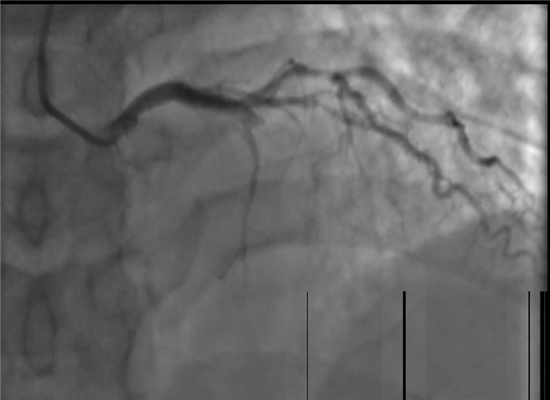

手术之前